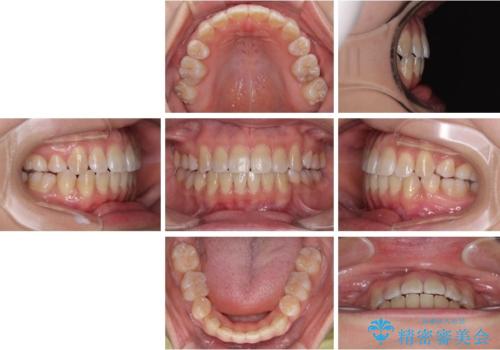

非接触の前歯と下顎のデコボコ ワイヤー装置による矯正治療

- 2年6ヶ月

舌のトレーニングは継続して行ってもらっているため、開咬や抜歯したスペースの後戻りはなく、経過は良好です。